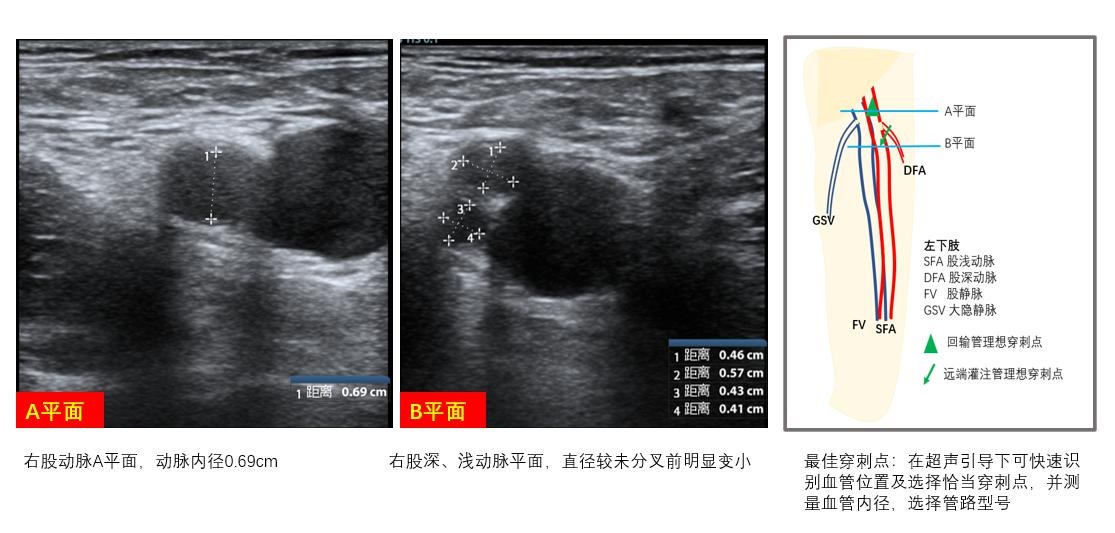

② VA-ECMO急诊VA-ECMO血管通路的选择通常是股静脉-股动脉途径,其中,静脉超声探查同VV-ECMO。对股动脉和股浅动脉超声探查包含以下内容:

B、最佳穿刺点定位观察拟穿刺动脉与伴行静脉之间的位置关系,寻找最佳穿刺点,若超声发现同侧股动静脉之间的距离较近或呈上下叠加关系,则需考虑引流管和回输管分别左、右双腿放置,避免穿刺置管造成局部血管损伤及其他并发症的发生(图 11)。

C、动脉直径测量拟置管动脉血管的内径,选择合适的动脉管路型号,并可根据血管内径与拟置入管路外径之间的大小关系预估肢体远端肢体缺血可能,评估远端灌注管放置必要性,并可根据血管具体情况预估置管困难程度制定置管策略,如经皮穿刺、半切开、切开等,做好置管预案(图 12)。

|

| 图 12 动脉置管策略 |